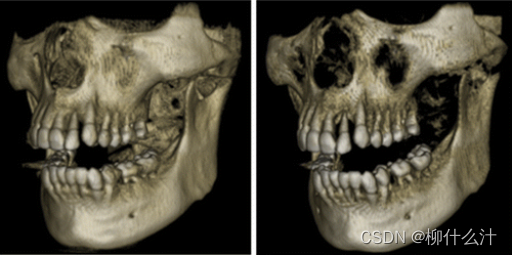

除了二维切片,还有三维渲染。可以对表面渲染和体积渲染进行区分。表面渲染(也成为间接体积渲染)是一种将图像数据转化为几何基元并进行渲染的技术,因此可能会出现一些信息的损失,因为它只显示阈值区域的表面。

用不同的阈值进行表面渲染。一个“从x到y的阈值”意味着只有x和y之间的灰度值可以保留用于可视化

第二张图是不同阈值进行的体积渲染。